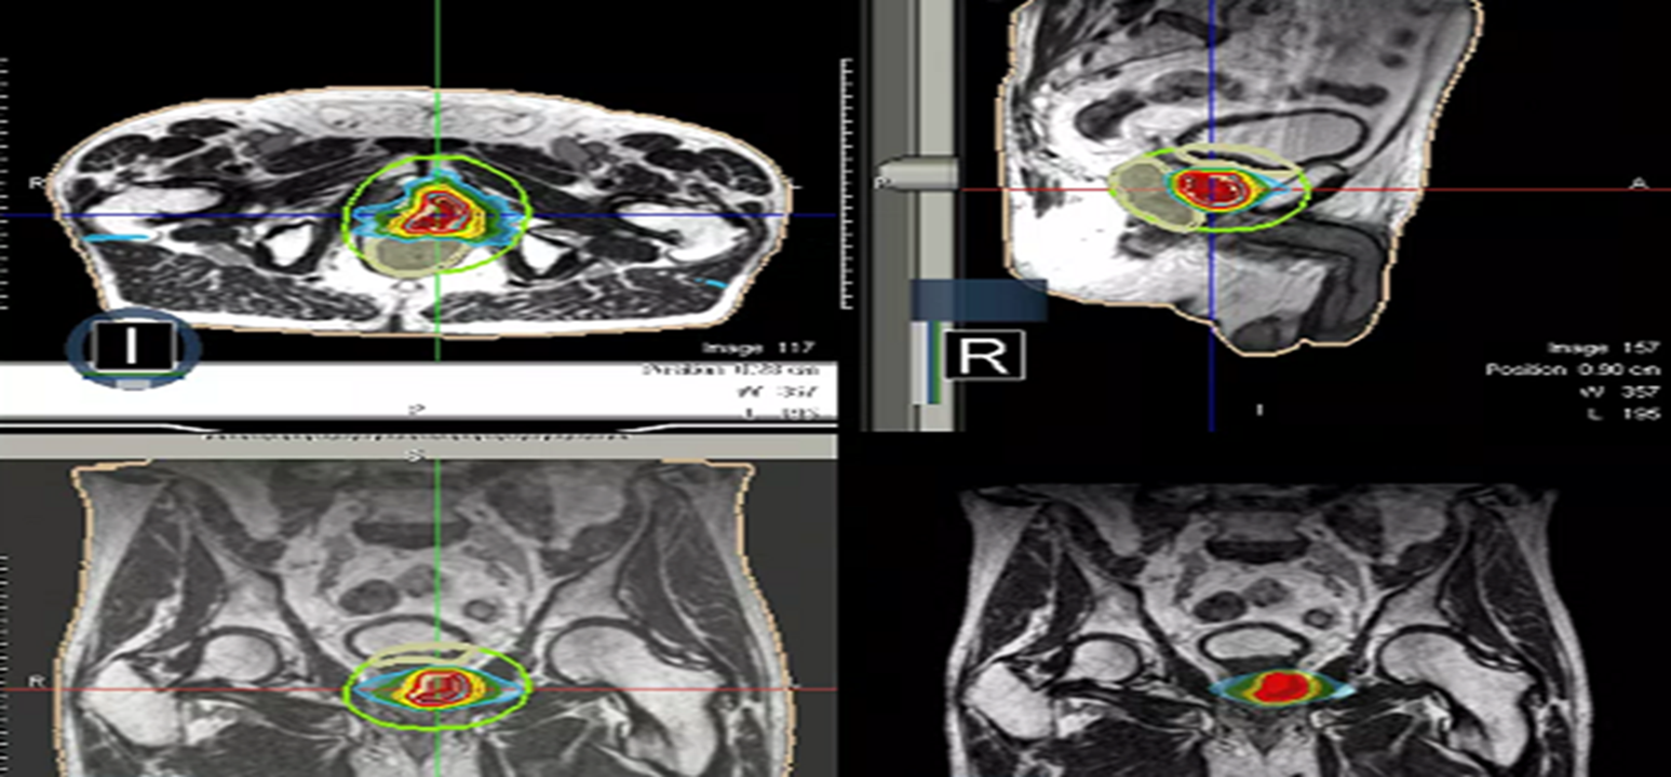

At each session, daily adaptation was performed to account for changes in the position of the prostate and for variable bladder and bowel filling. Figure 1 and figure 2 illustrate the typical differences seen between the original planning MRIdian scan and that seen on the day of treatment due to day-to-day organ movement. Figure 3 and figure 4 illustrate how these movements were accommodated with the on-table plan adaptation.

Fig 1: Original planning MRIdian scan

Fig 2: MRIdian scan at fraction 3, prostate position changed due to larger rectal diameter secondary to gas and smaller bladder

Fig 3: Prostate SABR delivery plan. Prostate volume covered by 95% isodose (green line, red arrow). Tight conformality at rectal/prostate boundary (white arrow), and rapid drop off of high dose (50% isodose, green line, green arrow) to optimise dose delivery to the prostate and limit dose to the rectum, reducing the risk of toxicity

Fig 4: Fraction 3, adapted plan, optimised for anatomy of the day. Prostate volume covered by 95% isodose (green line, red arrow). Tight conformality at rectal/prostate boundary (white arrow), and rapid drop off of high dose (50% isodose, green line, green arrow) to optimise dose delivery to the prostate and limit dose to the rectum, reducing the risk of toxicity